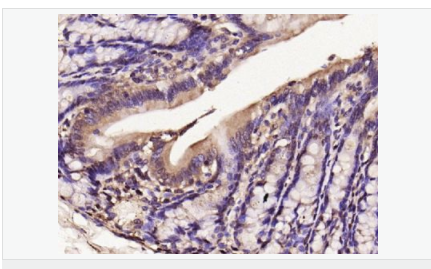

產(chǎn)品應用WB=1:500-2000 IHC-P=1:100-500 IHC-F=1:100-500 Flow-Cyt=1μg/Test ICC=1:100-500 IF=1:100-500 (石蠟切片需做抗原修復)

免 疫 原KLH conjugated synthetic peptide derived from human iNos/Nos-2:1051-1153/1153